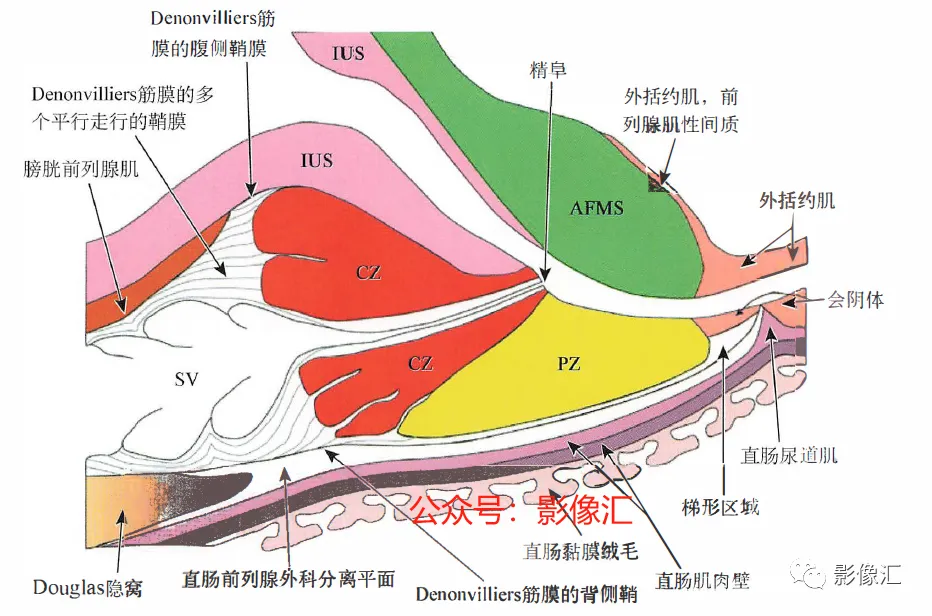

上图,前列腺中线正中矢状切面,显示中央带(CZ)、外周带(PZ)和前列腺肌性间质(AFMS)。注意在CZ底部的精囊喙水平缺少前列腺包膜。Denonvilliers筋膜由多个平行走行的鞘组成,头尾走行。在组织学上,其具有平滑肌纤维,血管和神经的纤维弹性结缔组织。在其侧缘,与Farabeuf骶骨-直肠-生殖-膀胱耻骨筋膜的外侧鞘及膀胱输精管动脉的横向隔膜融合。直肠-前列腺手术分离沿形成Denonvilliers筋膜的鞘复合体背侧进行操作。Denonvilliers筋膜是一层疏松的结缔组织。

AFMS:前列腺肌性间质;CZ:中央带;PZ:外周带;SV:精囊;IUS:尿道内括约肌。

根据示意图可显示五个筋膜(图2.16和图2.17)。上图,前列腺中线正中矢状切面,显示中央带(CZ)、外周带(PZ)和前列腺肌性间质(AFMS)。注意在CZ底部的精囊喙水平缺少前列腺包膜。Denonvilliers筋膜由多个平行走行的鞘组成,头尾走行。在组织学上,其具有平滑肌纤维,血管和神经的纤维弹性结缔组织。在其侧缘,与Farabeuf骶骨-直肠-生殖-膀胱耻骨筋膜的外侧鞘及膀胱输精管动脉的横向隔膜融合。直肠-前列腺手术分离沿形成Denonvilliers筋膜的鞘复合体背侧进行操作。Denonvilliers筋膜是一层疏松的结缔组织。

AFMS:前列腺肌性间质;CZ:中央带;PZ:外周带;SV:精囊;IUS尿道内括约肌。两个矢状面走行筋膜:Farabeuf骶骨-直肠-生殖-膀胱-耻骨鞘(左右各一);三个横轴面走行筋膜:脐-膀胱前筋膜;“生殖动脉隔”;直肠中动脉的隔(Septum of the mid-hae-morrhoiclal artery)。在前列腺,这些鞘也被称为“Retzius前列腺周围筋膜”“前列腺周围筋膜”“前列腺侧带”,或者最近称为“盆内筋膜腹侧面” 。这些筋膜覆盖腺体的侧面和腹侧,在腹侧与前纤维肌性间质(AFMS)融合。供血血管和支配神经在这些鞘内走行。一旦解剖前列腺后部或直肠前平面,这些鞘在前列腺的两侧形成手术分离平面。前列腺“本身”不具有包膜结构;所谓的包膜只是腺样间质聚集所致,而且个体间变异度很大,同时在某些点上并不存在,从而构成McNeal所述的解剖薄弱区域。因此,从实际的角度来看,我们认为虽然前列腺没有自己的包膜结构,但其确实有三个“假包膜":